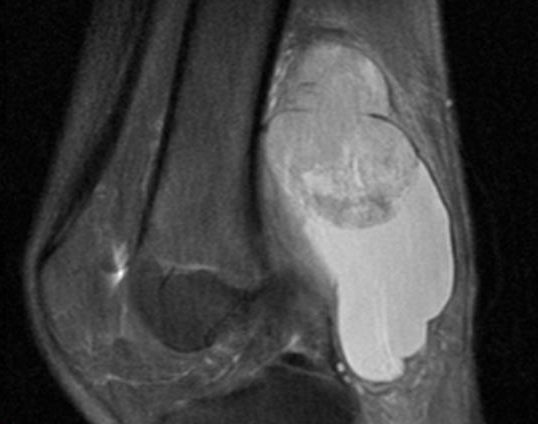

При появлении признаков синовиальной саркомы важно незамедлительно обратиться к врачу. Это значительно увеличивает шансы на успешное выздоровление. Для точной диагностики используются следующие методы:

- для выявления метастазов применяются МРТ, УЗИ, КТ и лапароскопия.